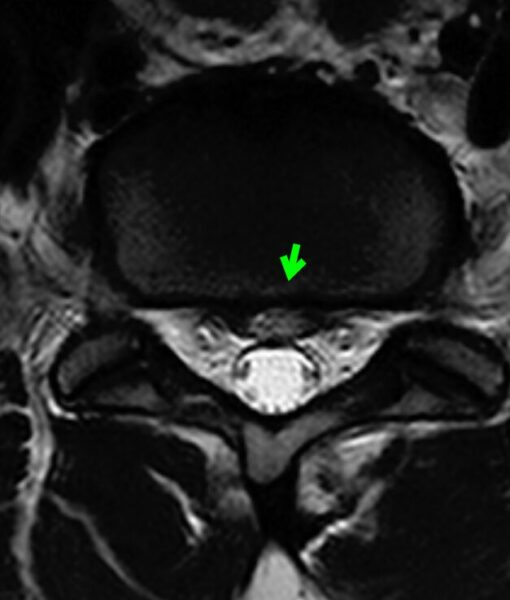

事故から6か月後のMRI

6か月後のMRIでは、

ヘルニアのサイズ変化を確認できました。

このように、

事故直後、3か月後、6か月後のMRIを比較することで、

椎間板の輝度変化

ヘルニアサイズの変化

症状との関連

を客観的に評価できる場合があります。

その結果、

今回の事故を契機にヘルニアが悪化した可能性を考える、

重要な材料になります。

〔画像③:事故後6か月MRI〕